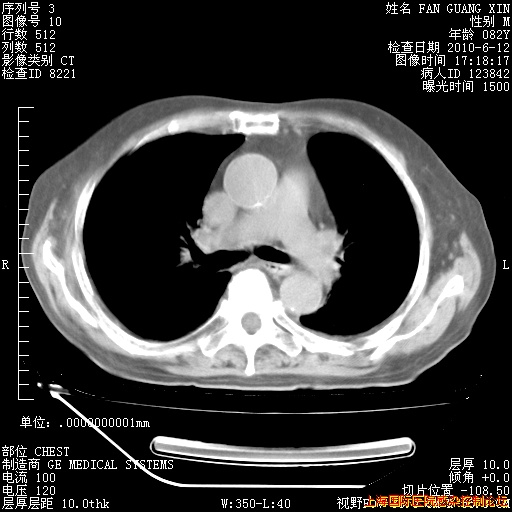

补发6月12日肺部CT肺窗

6月12日肺窗

6月12日纵膈窗

整整相隔30天的肺部CT好像有所好转啊。甲强龙减量第3天,需要观察体温。

海管,自昨日你和我通完话后,不知您岳父消化道症状有无缓解?体温怎样?阅读7.12日胸部ct,个人认为目前激素治疗是有效的,甲强龙减量是适宜的。因在抗痨治疗,需密切观察肝功、肾功能和血常规。不过,老年、长期住院和大量使用激素,很担心菌群失调发生